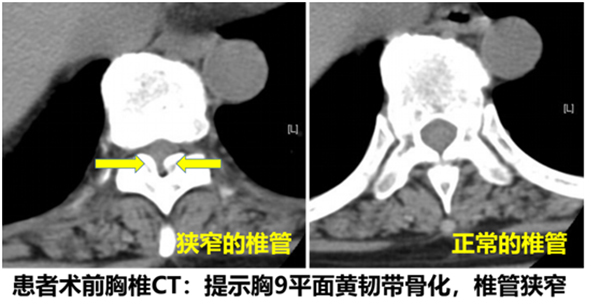

57岁的周女士也不幸得了胸椎管狭窄症,一边是日益加重的胸腹部束带感,就是感觉胸口及肚子上被布带勒紧的感觉,还有双下肢无力、麻木、足不能背伸、不能行走,已经出现截瘫的症状,并且越来越严重,只能长期卧床;一边是手术的极大风险,多地多处就诊无果后,慕高增鑫副院长之名到我院脊柱专家门诊就诊,被诊断为“胸椎管狭窄症、胸9黄韧带骨化症、双下肢不全瘫”。

骨化的黄韧带压迫硬膜囊,增加了原本就手术难度大的胸椎管减压手术的风险,术中触压脊髓极易出现不可逆的伤害,导致患者彻底瘫痪,就像排雷时不慎触发了引线,后果不堪设想。 胸椎管狭窄症指的是先天性或后天退变因素等导致的胸脊髓及神经根受压导致相应的临床症状和体征的疾病。胸椎管和胸脊髓特殊的解剖和生理特点导致该疾病致瘫率高、手术风险极大,许多脊柱外科医生将胸椎手术视为“手术禁区”。 周女士也是幸运的,自从我院成为东南大学附属中大医院溧水分院以来,在高增鑫副院长的带领下,骨科先后开展了经皮脊柱全内镜下治疗颈肩痛、腰腿痛等一系列脊柱内镜手术。脊柱内镜手术只需要在局部麻醉下,利用“钥匙孔”大小的手术切口(约6-8mm小孔),通过脊柱内镜设备解决深藏在脊柱中的病灶,这是目前解决脊柱疾病的首选技术。